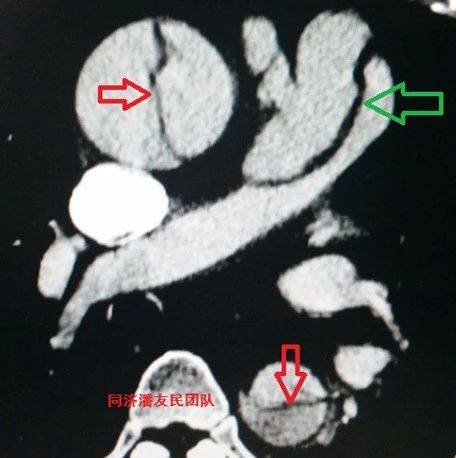

急性主动脉夹层是一种危及生命的急症,患者临床预后很差,死亡率高达50%左右。因此,了解急性主动脉发病的时间生物规律,可能有助于找出其触发因素并有效预防。 7月14日,华中科技大学同济医学院附属同济医院心脏大血管外科魏翔等在Heart杂志上发表的一项单中心研究显示,急性主动脉夹层发病有明显的季节、月份和昼夜规律。 总体上,寒冷的冬季(12月)是急性主动脉夹层发病高峰,而夏季(6月)发病率最低。